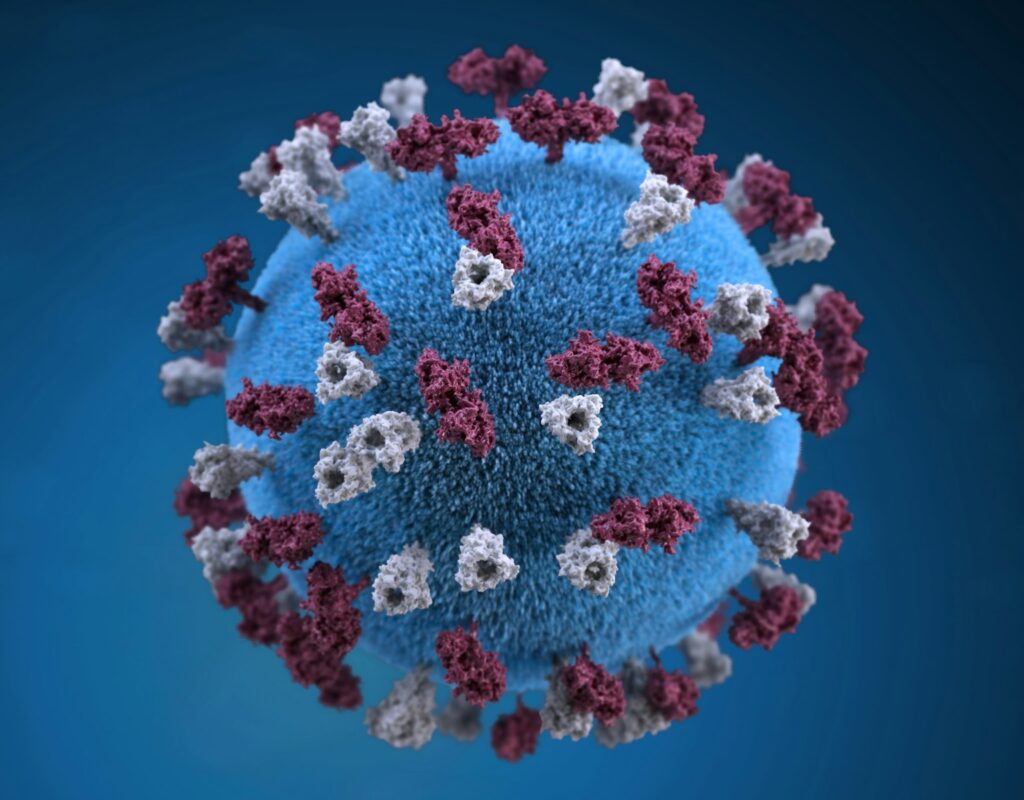

The human body is an intricate marvel, equipped with a sophisticated defense mechanism known as the immune system. Think of your immune system like a hardworking security team: Day and night, with zero breaks, it’s scanning for potentially dangerous intruders. It diligently wages battle against harmful bacteria and viruses, often without us even realizing the silent wars being fought within.

However, these defenses can occasionally glitch, mistakenly identifying the very tissues they are designed to protect—our own bodily cells—as foreign invaders. When this critical error occurs, an individual might be dealing with what is known as an autoimmune disease. Konstantin Balashov, MD, PhD, the director of the Boston Medical Center Multiple Sclerosis Center, explains that this is when the immune system turns on itself.

9. **Recurrent Infections: Unmasking Immune Imbalance**A pattern of frequent and recurring infections, such as persistent colds, sinusitis, or urinary tract infections, can often indicate a deeper imbalance within the immune system. While it might seem counterintuitive for an immune system “attacking itself” to also be weak, in autoimmune diseases, the immune response can be misdirected or overall compromised. This vulnerability can be due to the disease process itself, which may deplete certain immune resources, or from immunosuppressive treatments designed to manage the autoimmune condition.

When the body is constantly battling internal threats from autoimmunity, its capacity to effectively fend off external pathogens can be diminished. This leaves individuals more susceptible to infections that a healthy immune system would typically handle with ease. Recognizing a consistent pattern of infections that seem to strike with unusual frequency or severity is therefore a crucial signal that warrants attention from healthcare professionals.

Monitoring for this pattern of recurring infections, particularly if they are challenging to clear or become chronic, can serve as a vital clue. It prompts a deeper evaluation of immune function and resilience, guiding healthcare providers to consider underlying autoimmune disorders and to tailor management strategies accordingly. Addressing the root cause of immune dysregulation is key to reducing susceptibility to such repeated infections.